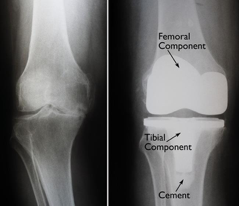

Sebelum menjalani operasi penggantian lutut, pasien terlebih dahulu akan menjalani pengobatan nonbedah. Pengobatan tersebut dapat berupa pemberian obat-obatan, injeksi sendi, ataupun pemberian alat penyangga untuk membantu pasien beraktivitas menggunakan lututnya. Namun perlu diingat, tulang rawan sendi tidak dapat tumbuh kembali dengan sendirinya dengan terapi obat dan fisik yang tersedia. Jika metode pengobatan nonbedah sudah tidak efektif meredakan nyeri dan meringankan keluhan sehingga mengganggu aktivitas sehari-hari, pasien dapat menjalani operasi penggantian lutut (TKR). Pada operasi ini, bagian sendi yang rusak akan dibuang dan dilapisi dengan implan berbahan titanium dan bantalan berbahan polyethylene. Tujuannya adalah untuk menghilangkan nyeri dan mengembalikan fungsi sendi lutut, agar pasien tetap dapat menggunakan lututnya seperti biasa.

•    Pemasangan implant metal. Bagian tulang rawan dan tulang yg sudah dibuang akan digantikan lapisan implant metal yang akan membentuk kembali permukaan sendi. Implant metal ini biasa dipasang menggunakan lapisan semen.